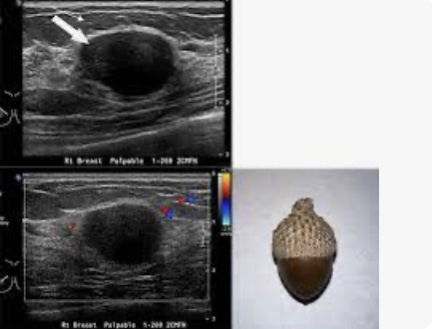

Acorn Cyst

• An “acorn” cyst is lined with papillary apocrine metaplasia:

• Which can form a mural nodule:

• The nodule in an acorn cyst is less echogenic than papillomas or papillary carcinomas:

• Is usually concave, following the contour of the cyst (thus the appearance of a cap on an acorn) instead of convex, and does not have a vascular stalk

• The mural nodule caused by papillary apocrine metaplasia:

• Also would not extend into the duct as the papillary lesion shown in the image does